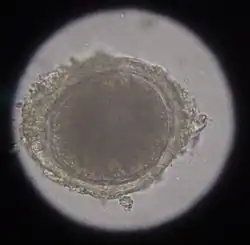

In the case of worms in vomit, the diagnosis can already be made without special examinations. A roundworm infestation can be detected with relative certainty by microscopic detection of the eggs extracted from the feces using the flotation method.

Infection with hookworms often remains asymptomatic in cats. In more severe infestations, they can cause emaciation, anemia or diarrhea. As with roundworms, the infection is detected by detecting the eggs in the feces using a flotation method. They are oval, smaller than roundworm eggs (about 60×40 μm in size) and furrowed stages are already visible inside when the eggs are laid.

In the same animal, usually only two to ten cat tapeworms are found, and they excrete about four to five limbs daily. These elongated trapezoidal structures may already be visible to the naked eye in the anal region. The coated oncospheres, which are about 35 μm in size, can be detected in the feces using flotation methods. In one study, an infestation rate of 25.9% was determined in autopsies, of which only 10% were detected by flotation and 27% by centrifugation.[10] In addition, the eggs cannot be distinguished morphologically from those of other members of the taeniidae (including the fox tapeworm).